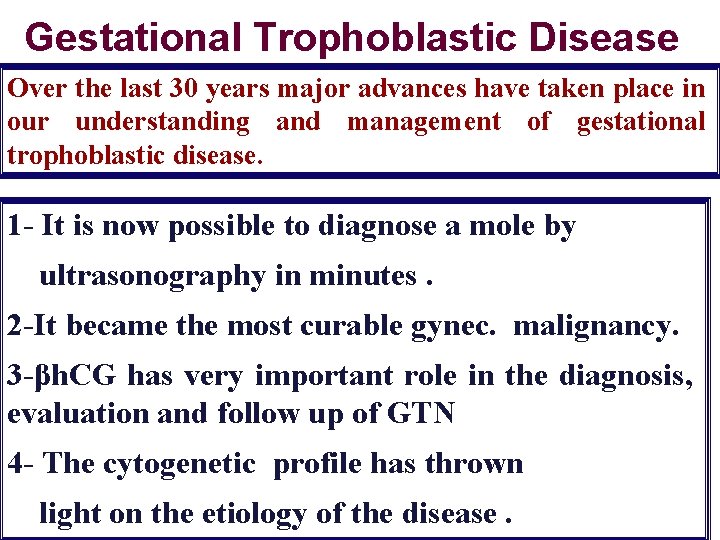

Gestational Trophoblastic Disease Over the last 30 years major advances have taken place in our understanding and management of gestational trophoblastic disease. 1 - It is now possible to diagnose a mole by ultrasonography in minutes. 2 -It became the most curable gynec. malignancy. 3 -βh. CG has very important role in the diagnosis, evaluation and follow up of GTN 4 - The cytogenetic profile has thrown light on the etiology of the disease.